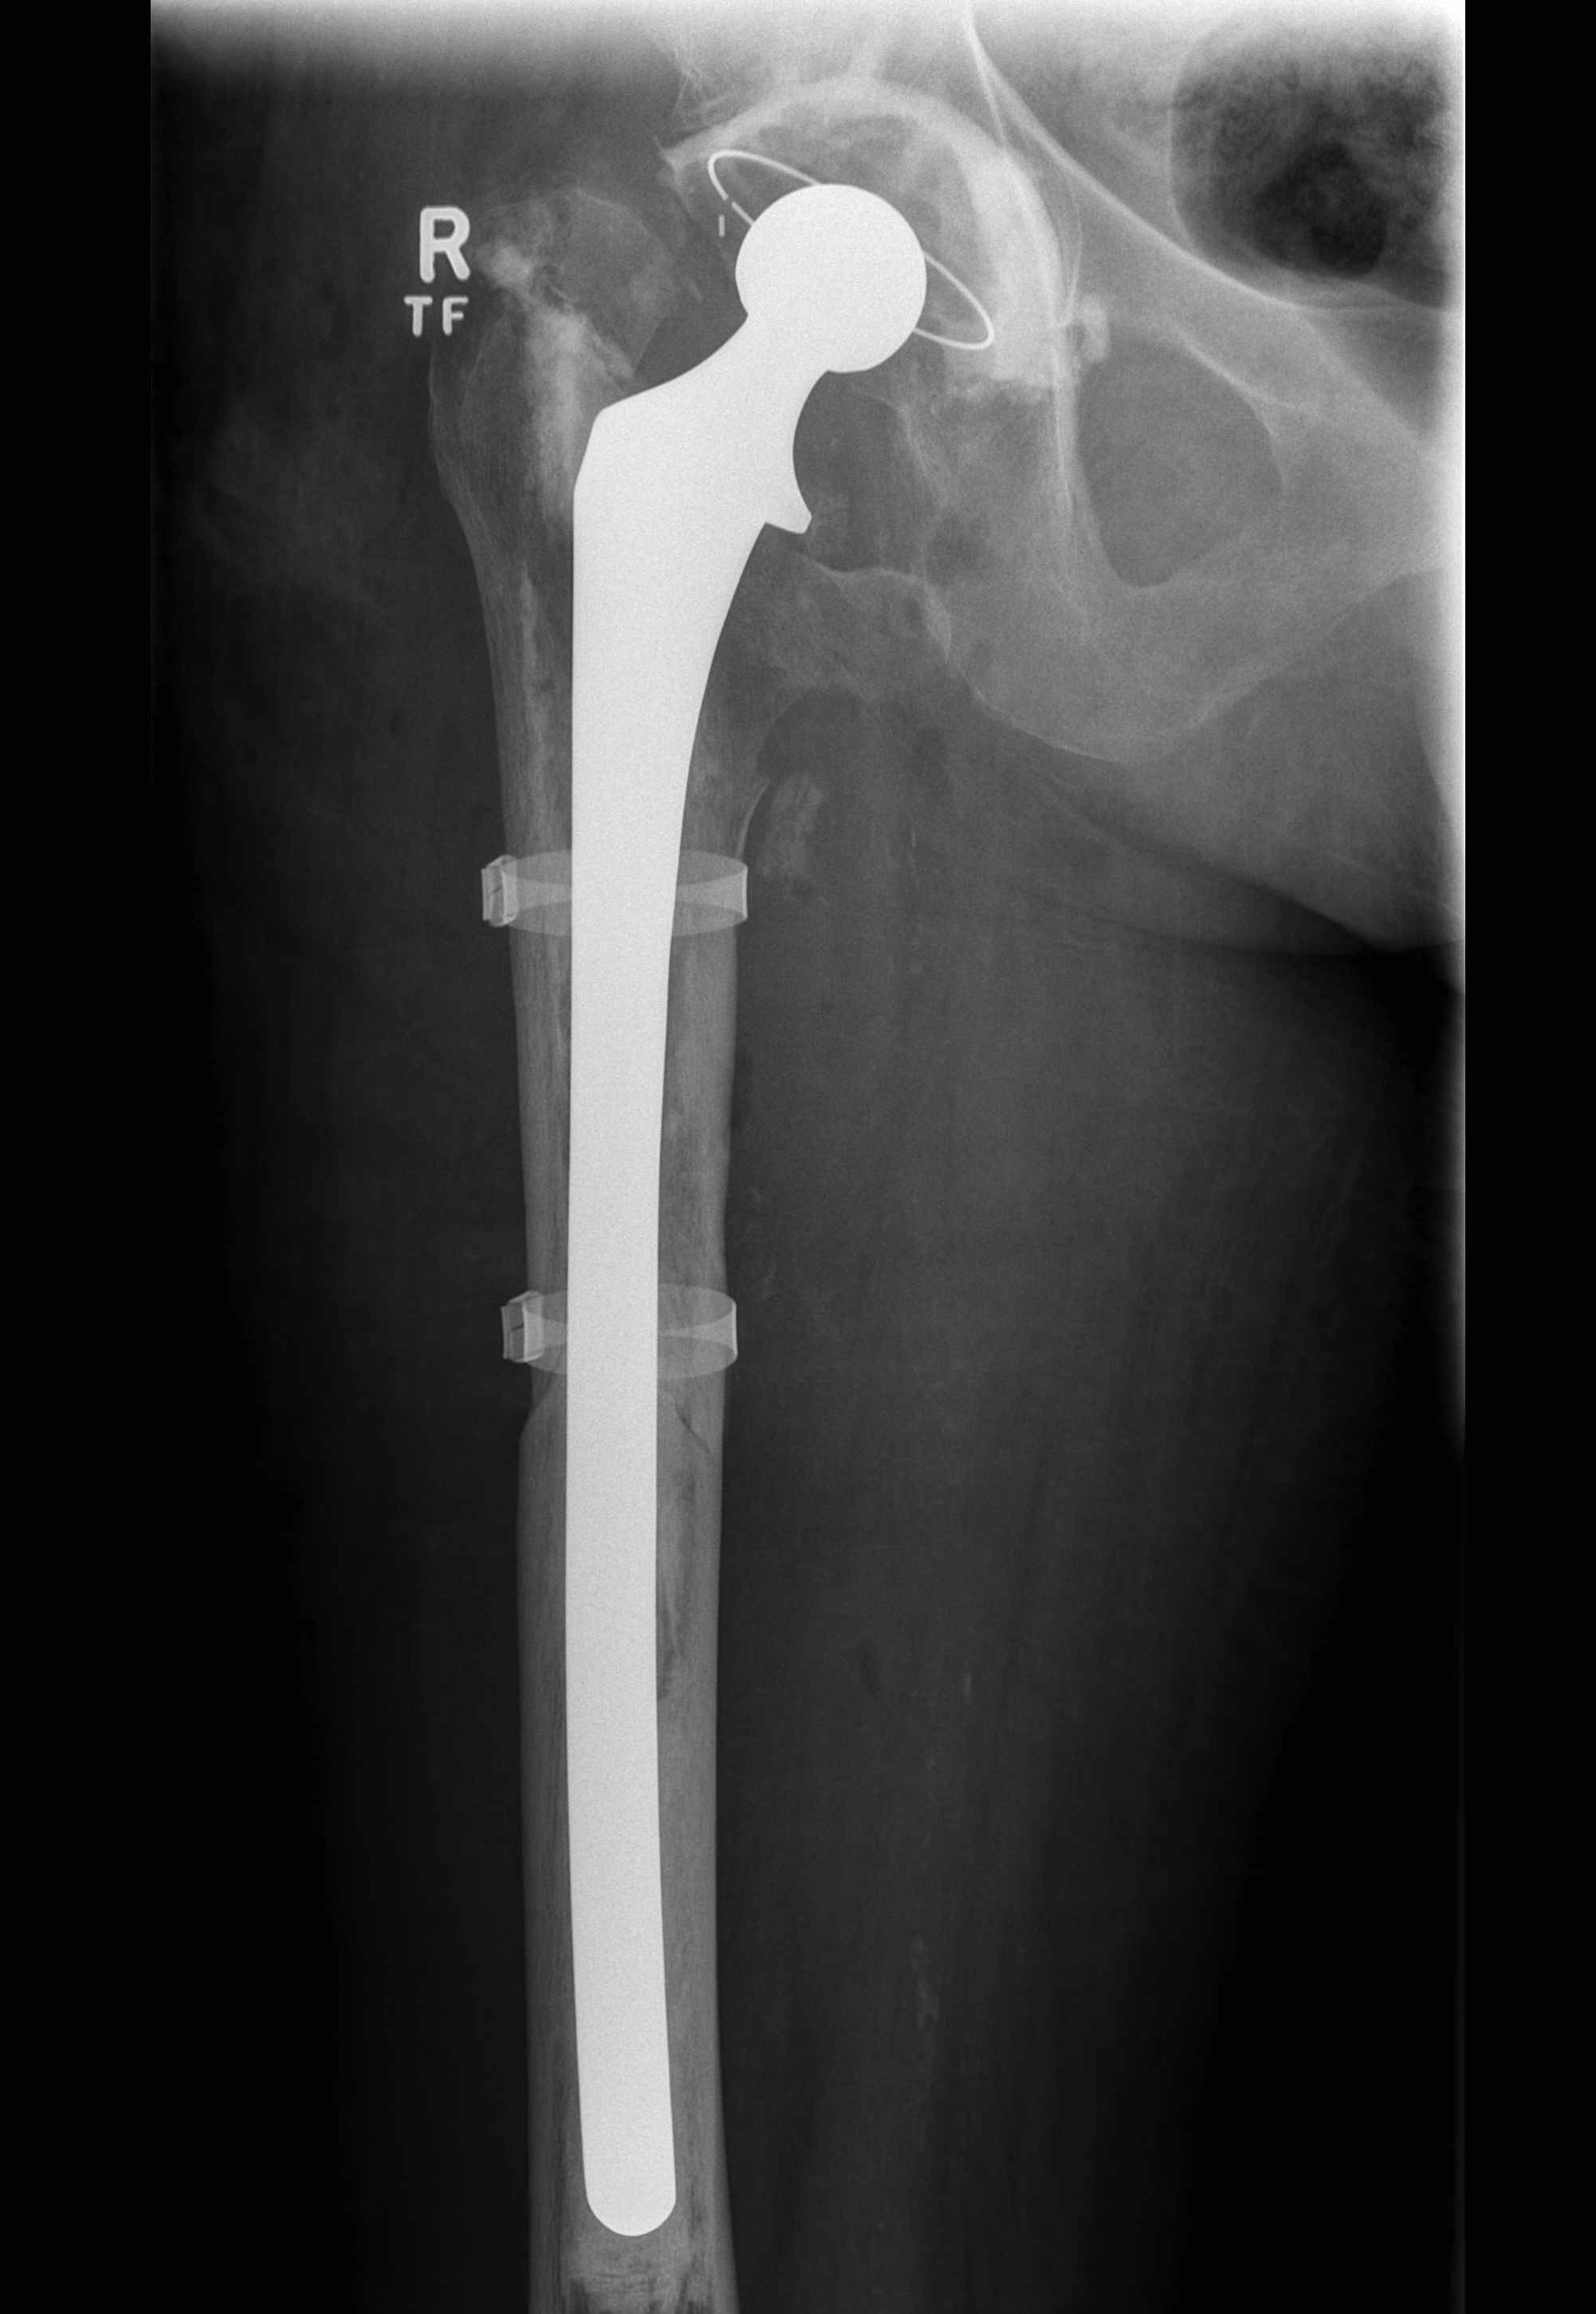

Long stem uncemented revision

A. Revision arthroplasty with long stem femoral implant +/- plate +/- cortical strut allograft

- distal fit (cemented / uncemented)

- must bypass distal extent of fracture by at least 2 cortical diameters

- long stem modular revision implants +/- plate +/- cortical strut